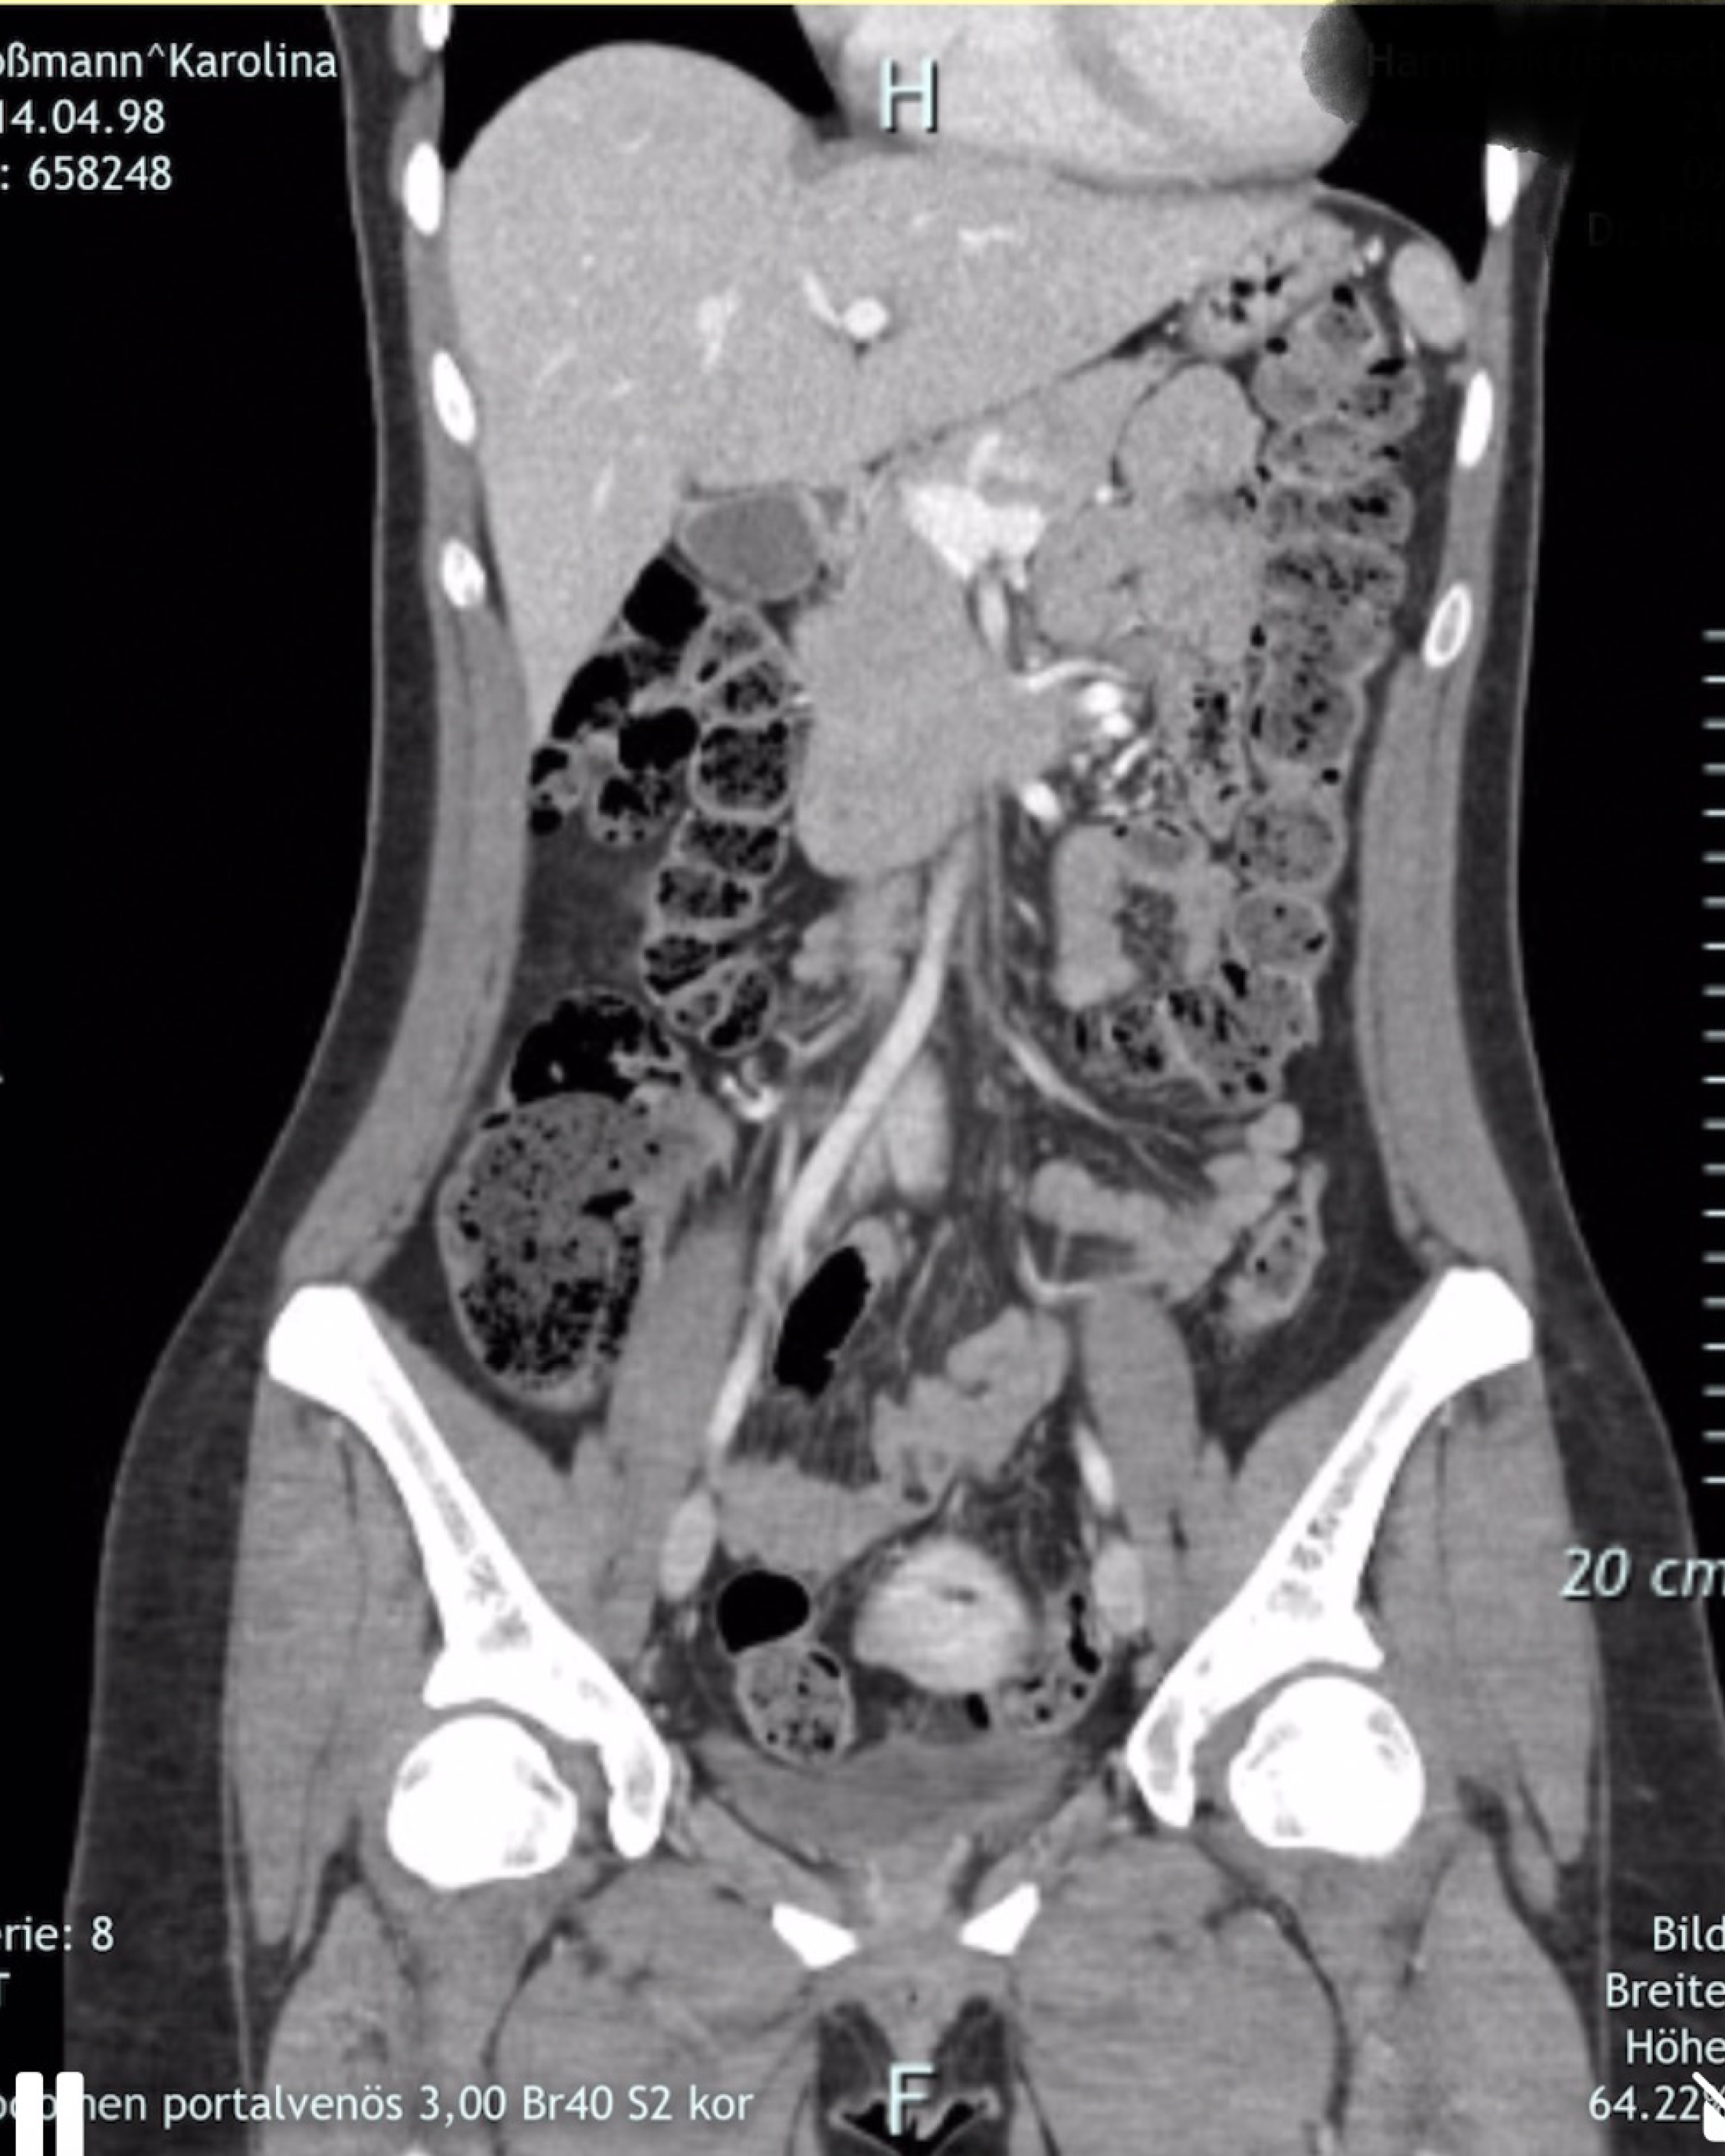

Von hinten durch die Brust ins Auge beschreibt einen unnötig komplizierten Zugangsweg. Zugleich ist es dieser unmögliche Schuss, der präzise den ganzen Körper durchdringt. In einem CT wird dieses Durchdringen plötzlich möglich und leicht. Bilder von Körpern bauen sich Schicht für Schicht auf und ermöglichen Beobachtenden einen voyeuristischen Blick ins Innerste. Der Wunsch, durch die Schichten zu dringen und hinter die Oberfläche zu blicken, entsteht sowohl in der Malerei als auch in der Beziehung zum Objekt der Begierde. Doch weder die Leinwand noch das andere lassen sich komplett durchdringen oder verstehen. In ihrer Arbeit nähert sich Karolina Koßmann Körpern, Objekten und Ideen an, die sich immer wieder verflüchtigen. Wie nah können wir Werken und Sehnsüchten wirklich kommen?